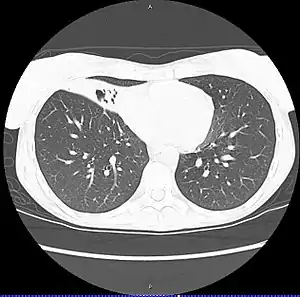

CT scan of patient with right middle lobe aspiration and Mycobacterium avium infection consistent with Lady Windermere syndrome | |

MAC usually affects patients with abnormal lungs or bronchi. However, Jerome Reich and Richard Johnson describe a series of six patients with MAC infection of the right middle lobe or lingula who did not have any predisposing lung disorders.[18][19]

The right middle lobe and lingula of the lungs are served by bronchi that are oriented downward when a person is in the upright position. As a result, these areas of the lung may be more dependent upon vigorous voluntary expectoration (cough) for clearance of bacteria and secretions.

Since the six patients in their retrospective case series were older females, Reich and Johnson proposed that patients without a vigorous cough may develop right middle lobe or left lingular infection with MAC. They proposed this syndrome be named Lady Windermere syndrome, after the character Lady Windermere in Oscar Wilde's play Lady Windermere's Fan. However, little research has confirmed this speculative cause.[20]

- Chest X-ray or CT scan showing evidence of right middle lobe (or left lingular lobe) lung infection